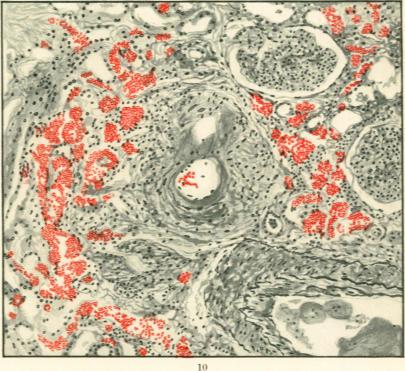

Specific Lesions of Peripheral Blood Vessels in Rheumatism.

Am J Pathol. 1926 May;2(3):235-250.11.